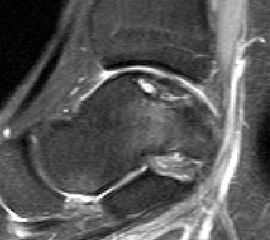

Im Laufe der Jahre hat sich die Magnetresonanztomographie (MRT) als sehr gute Option zur bildgebenden Diagnostik erwiesen. Die besonderen Vorteile liegen in der guten Beurteilbarkeit der Weichteilstrukturen und der Nichtinvasivität ohne Notwendigkeit der Verwendung von Röntgenstrahlen. Prinzipiell können alle geforderten Eigenschaften der Pathologie incl. der Veränderungen des subchondralen Knochens und des darüberliegenden Knorpels sowie der gelenkumgebenden Weichteilstrukturen visualisiert werden. Daher wird die MRT als Wichtigste anzufertigende Bildgebung angesehen 1720.

Die Standardsequenzen umfassen Fast-Spin-Echo (FSE) und Gradientenechosequenzen 22. Die Pulssequenzen umfassen typischerweise Protonendichte (PD) und fettunterdrückte Protonendichte Sequenzen (PD-FS) 17. In unserem eigenen Protokoll verwenden wir aktuell isotrope 3D-Gradientenechosequenzen (true FISP) (Abb. 3), protonendichte-fettunterdrückten Turbo-Spin-Echo-Sequenzen (PD-FS-TSE) (Abb. 4 und 5) und T1-gewichtete Spinechosequenzen (Abb. 6). Wichtig ist letztendlich die räumliche Auflösung als Funktion der Schichtdicke, dem Blickfeld (FOV) und der Bildmatrix 17.

Die Verwendung von intravenösem oder intraartikulärem Kontrastmittel kann die Diagnostik und Einteilung in eine Klassifikation erleichtern. Nach intravenöser Kontrastmittelgabe spricht die Aufnahme des Kontrastmittels im Interface zwischen osteochondralem Fragment und dem Fragmentbett für Granulationsgewebe im Grenzspalt. Wenn diese Kontrastmittelaufnahme in einer T2-Wichtung nicht stattfindet und das Signal unverändert bleibt, spricht dies für Flüssigkeit im Interface, was eine instabilere Situation bedeuten würde 23. Ebenso kann der Vaskularisierungsgrad des Fragmentes und damit die Vitalität abgeschätzt werden, dies ist allerdings nur eingeschränkt möglich 23. Bei intraartikulärer Kontrastmittelgabe kann die Integrität des Knorpels und der Dissektionsgrad des osteochondralen Fragmentes besser abgeschätzt werden. Ebenso kann eine Verbindung von subchondralen Zysten zum Gelenk beurteilt werden 19.

Trotz der vielfältigen Möglichkeiten der MRT ist die Beurteilung des Ausmaßes der knöchernen Beurteilung der Läsion teilweise schwierig. Die Ausdehnung des Knochenmarködems führt dabei manchmal zu einer Überschätzung der Läsionsgröße 24.